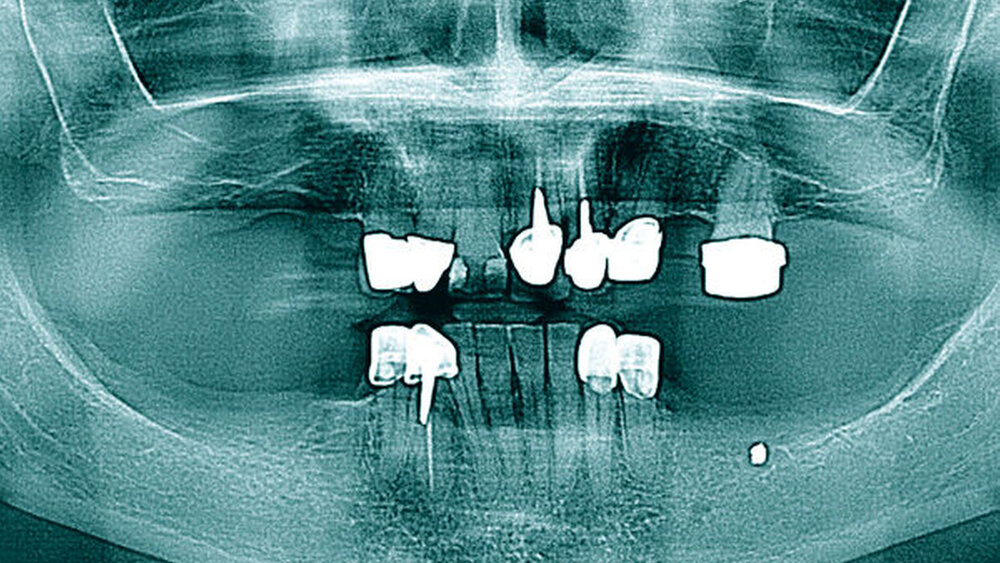

Radiologisch zeigt die erste Panoramaschichtaufnahme die präendodontische Ausgangssituation mit einer metalldichten Verschattung in regio 036. Die postendodontische Panoramaschichtaufnahme stellt die Wurzelfüllung mit dem überpressten Sealer periapikal und in Höhe des Mandibularkanals links dar (Abbildungen 1 und 2).